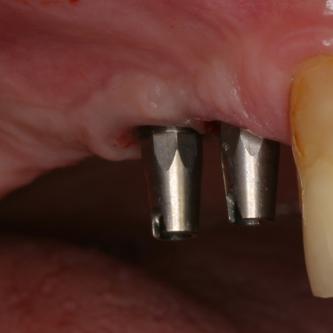

Exemple 9: Un cas complexe, 3 implants on été mis au niveau de la mandibule.

Exemple 9: Une barre est vissée sur ces 3 implants.